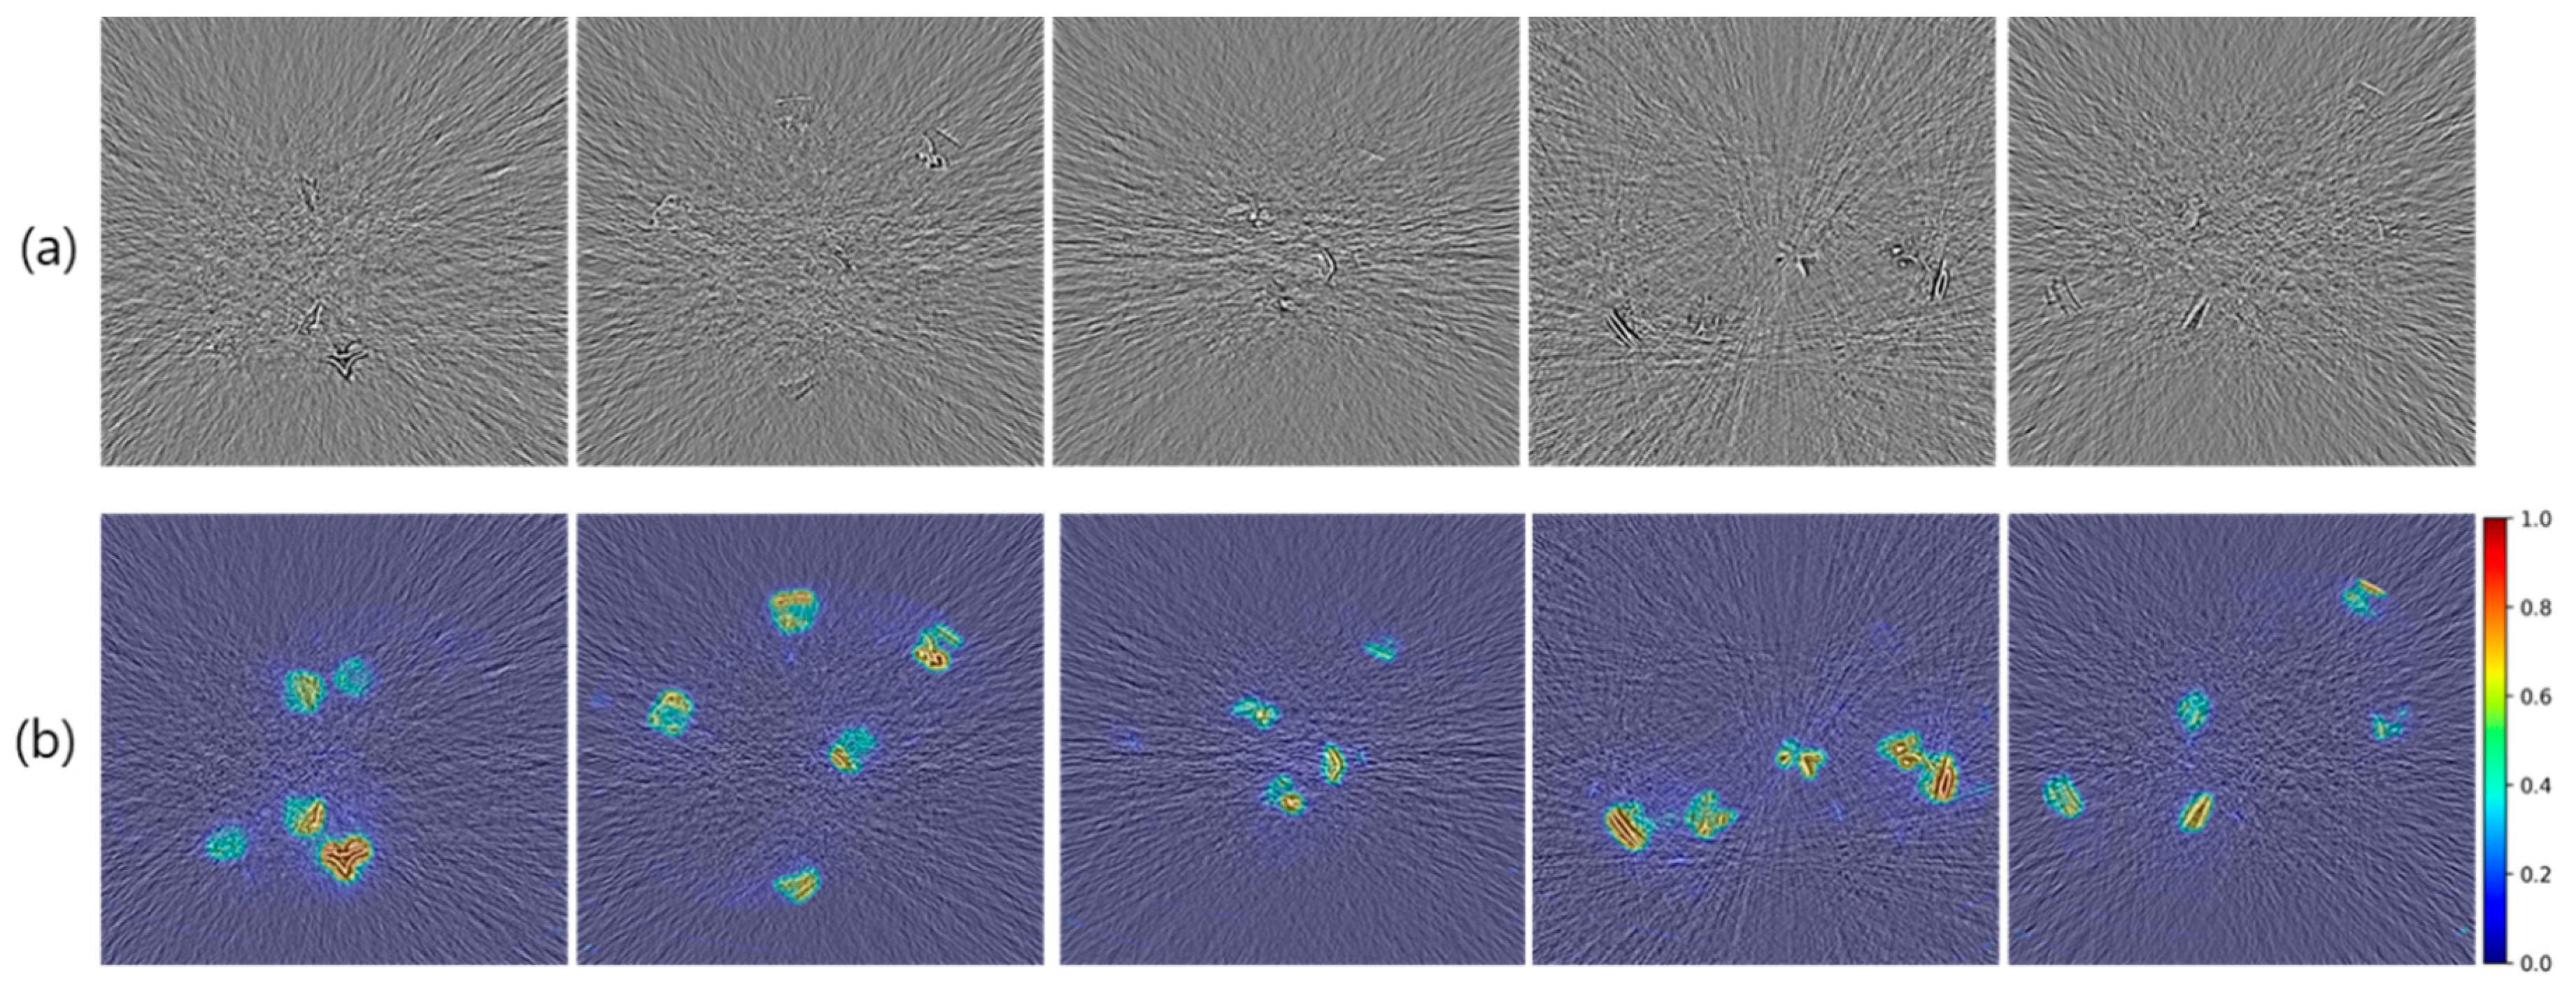

3.2. Verification of Prediction Performance with Heatmap